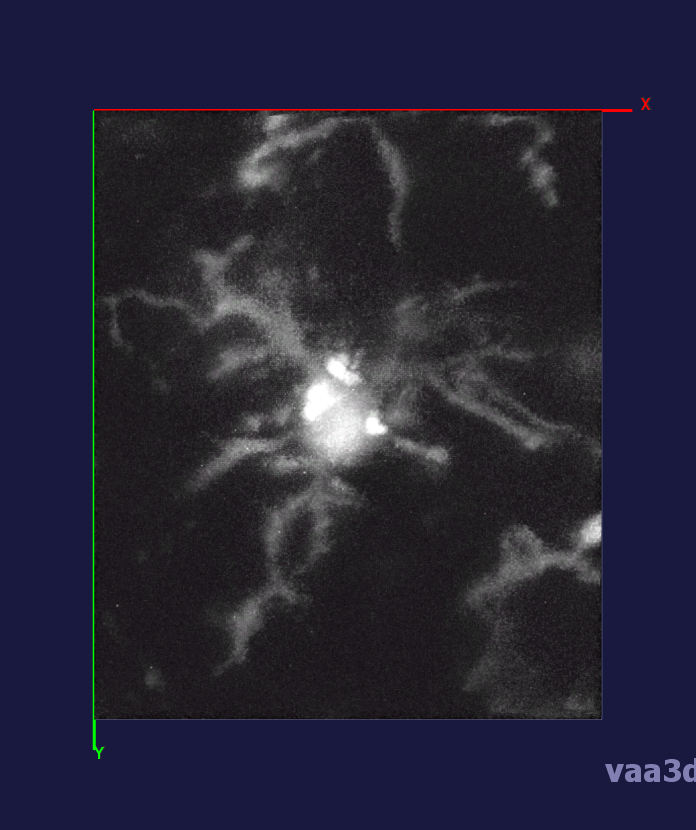

The 3D movies of microglia were imaged over 20 minutes with z-stacks taken at one minute intervals, containing single or multiple microglia per field of view. Some of the images were cropped from a larger field of view containing about 10 different cells and two images were imaged from a zoomed in view of one individual cell. The images ranged from a horizontal pixel width of .01 um and a vertical pixel width of .01 um to horizontal pixel width of .2 um and a vertical pixel width of .2 um. In the 3D images, there is variation in intensity contrast throughout the cell, non-structural noise, and fluorescence bleeding through z-stack due to the lengthy imaging technique which makes it difficult to visualize and process. The images were pre-processed using histogram equalization which increased the intensity throughout the cell but further increased noise in the background.

In our experiments, we compare the coupled TuFF-BFF microglia segmentation results with those given by L2S [21] and the Chan-Vese segmentation method [22]. The groundtruth in 3D was attained by manually tracing the object slice by slice from the z-stack. It must be noted that this was done by eye and could have some error. Figure 2 shows the visual comparison of the segmentation results for our dataset. Our result shown on the third column captures both the soma and processes. Figure 3 shows the Dice coefficient comparison of each segmentation method to the ground truth. Since the soma is much larger than the fine processes in the microglia, the processes have less volumetric impact on the similarity score. As explained in Section 1, segmenting the processes is important for quantifying the extension from the soma and its volume of surveillance. We use the Dice coefficient to quantitatively compare the ramification by taking the convex hull of the resulting segmentation. The Dice coefficient is a similarity measure that is computed using with where is the ground truth and is the compared image.

From Figure 4, the average Dice score for coupled TuFF-BFF was 0.77, compared to 0.53 for L2S [21] and .58 for Chan-Vese [22]. It must be noted that L2S required manual user initialization for each 2D image in the stack. While the Chan-Vese method has automatic seed selection, our coupled TuFF/BFF method was the only method that was a true 3D segmentation algorithm. L2S could not consistently capture the entire processes due to the intensity inhomogeneity throughout the object and background noise. The Chan-Vese segmentation could capture the extensions of the processes but did not work well with noise and attained false positives in the reconstruction. Since our method uses the tubular and blob information of the object to separate foreground and background, the segmentation only evolved within the object boundaries.